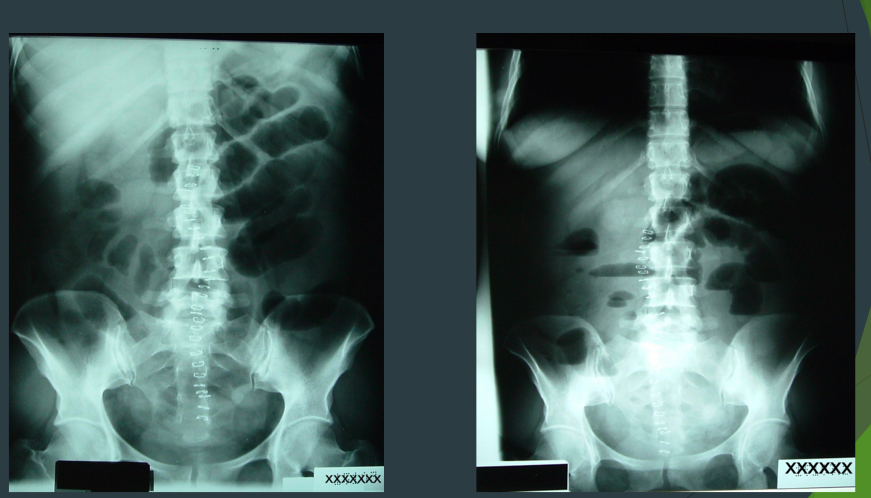

What are these two xrays showing?

Often occurs when?

Ileus

After surgery

What are these xrays showing?

Constipation (full of stuff/stool)